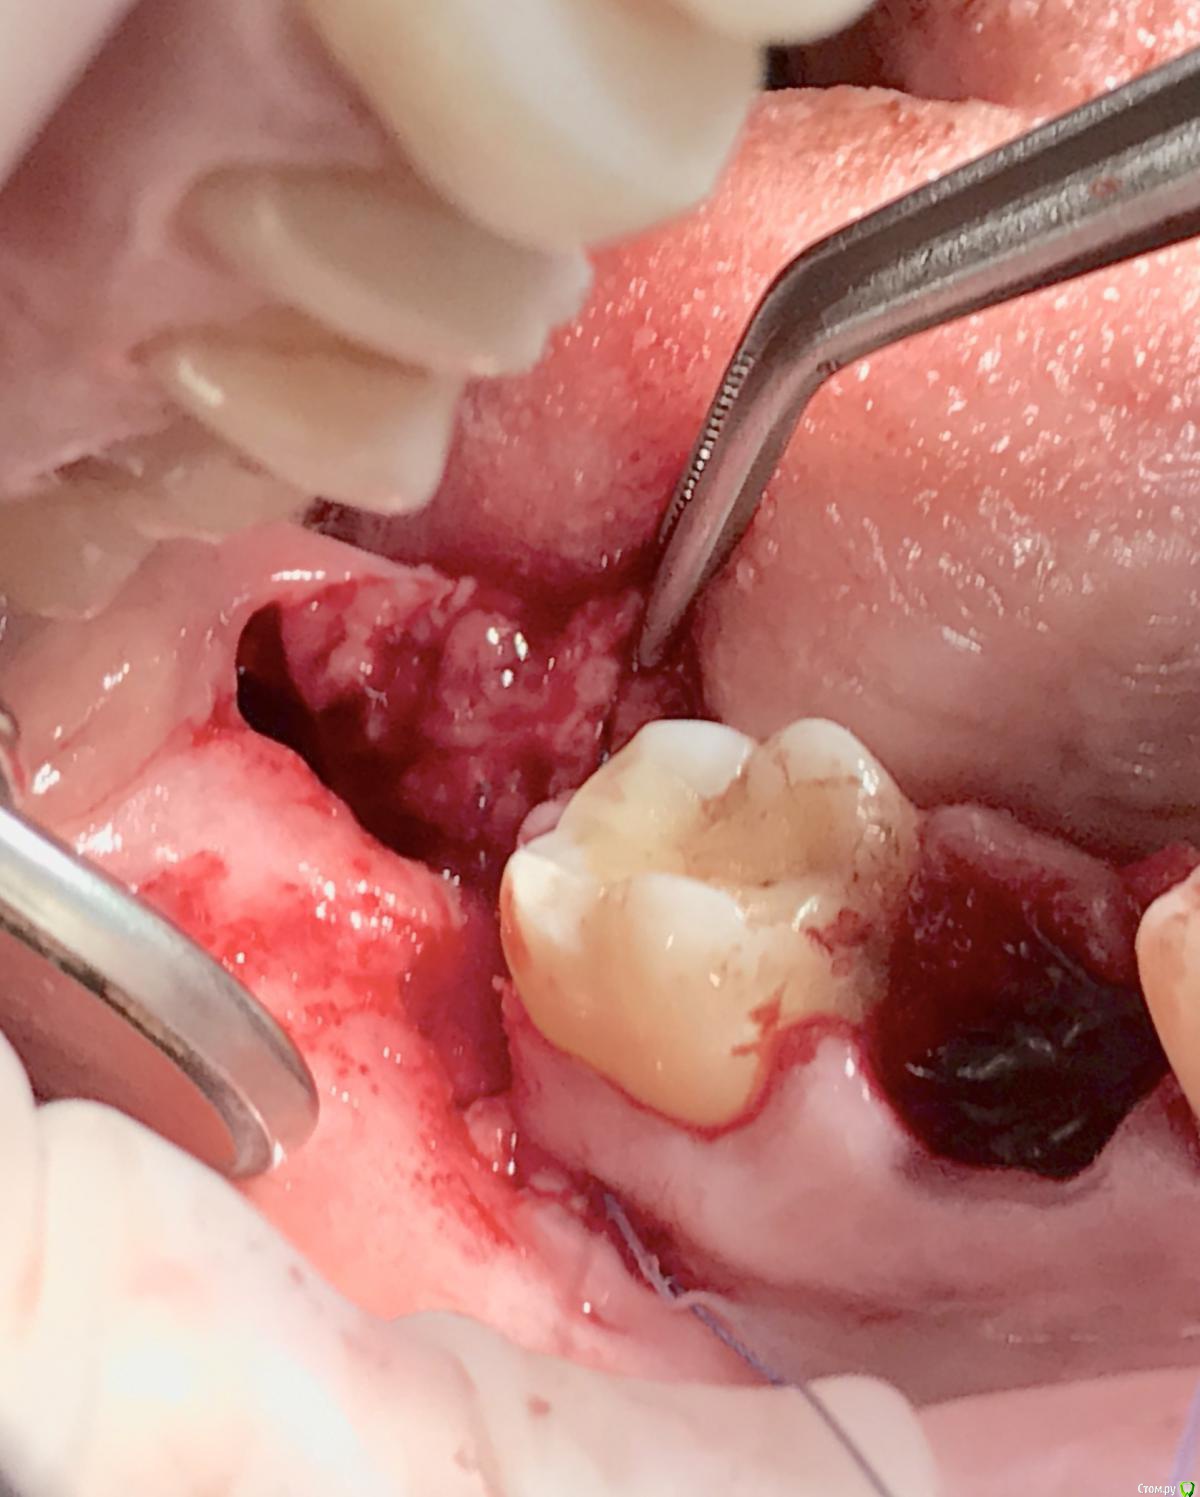

колесников Опубликовано 1 апреля, 2017 Автор Поделиться Опубликовано 1 апреля, 2017 Из свежего Ссылка на комментарий

колесников Опубликовано 2 апреля, 2017 Автор Поделиться Опубликовано 2 апреля, 2017 Тройной лоскут , вид через 5 -7дней. Снимок "до". И благодарность за скорое заживление 6 Ссылка на комментарий

колесников Опубликовано 16 апреля, 2017 Автор Поделиться Опубликовано 16 апреля, 2017 Иногда кажется ,что лоскут выделить язычно не возможно и наглухо ушить не удасться,особенно в случаях когда 8ка полностью прорезалась. Это только так кажется. Ссылка на комментарий